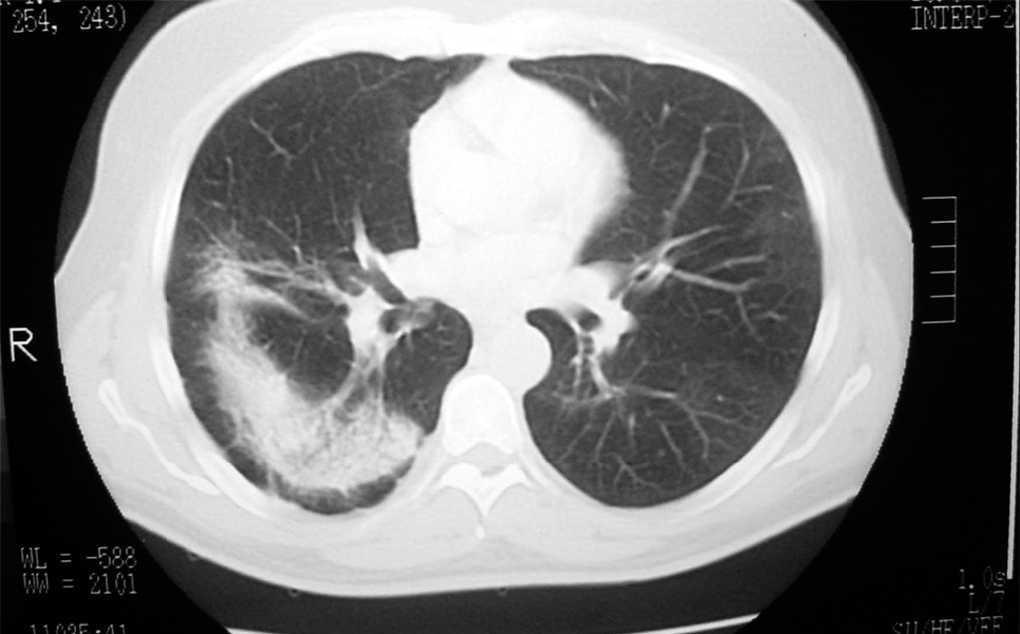

The patient brought a chest X-ray performed in February 2002 showing a bilateral alveolar pattern (fig. 1) and a chest computed tomography scan (fig. 2) taken during the period in which he had acute symptoms. There was consolidation of the left inferior lobes and right middle lobe. Laboratory analyses showed leukocytes 12300 mm 3 (eosinophils 33 %), platelets 576000 mm 3, globular sedimentation rate 105 mm/h, glucose 111 mg/dl and creatinine 0.9 mg/dl.

Figure 1.--CHEST X-RAY 2002: Bilateral alveolar pattern that affected the right upper lobe and apical segment of the right lower lobe and periphery of the left with increase of left hilum.

Chest X-rays were repeated in October 2003 and March 2004, showing disappearance of the acute infiltrates.